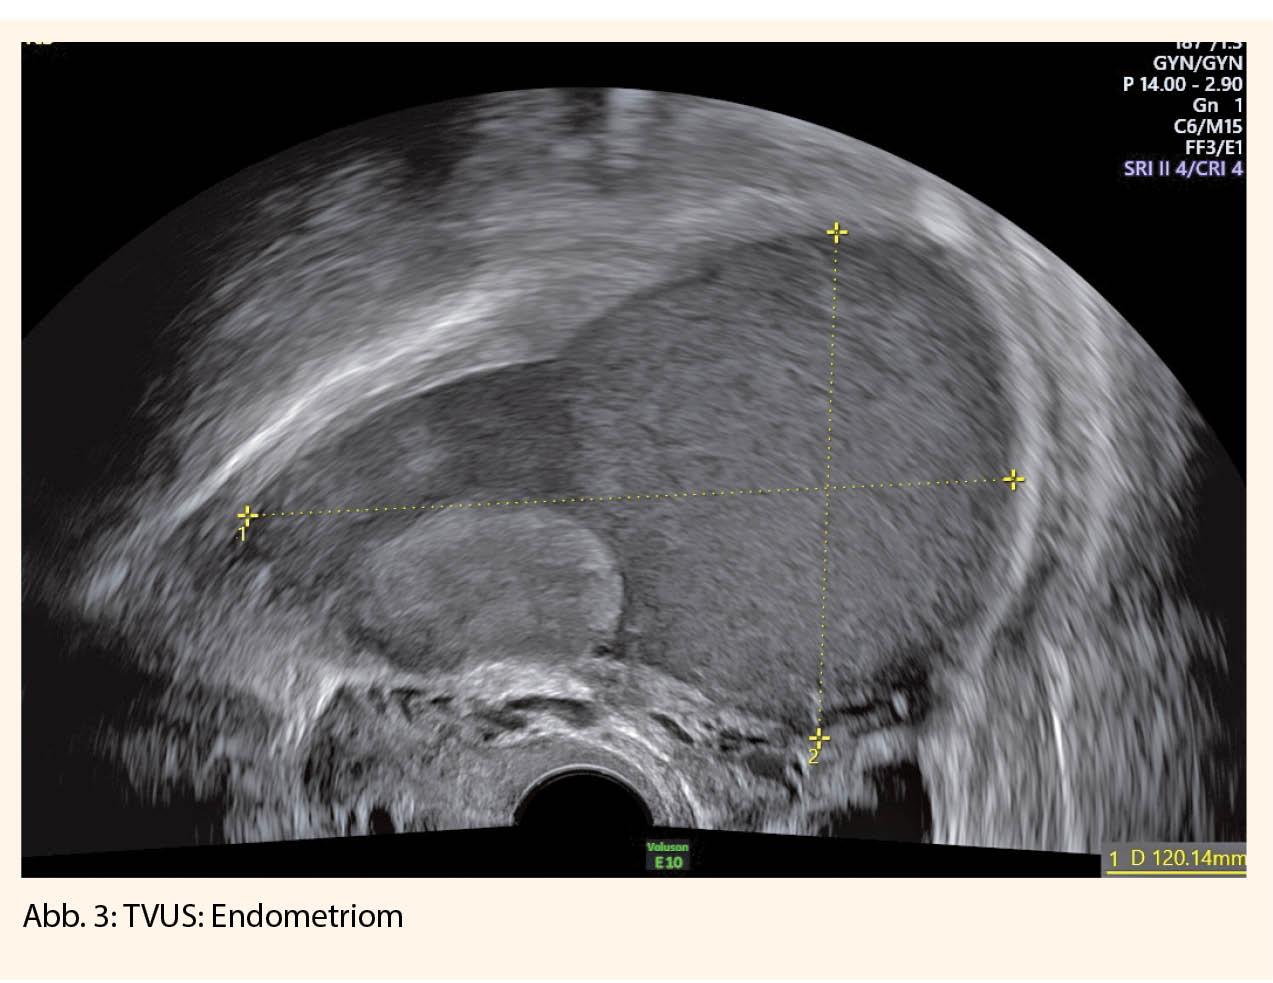

Die anschliessende klinische Untersuchung beinhaltet die Spekulumeinstellung, insbesondere Inspektion der hinteren Fornix vaginae, die bimanuelle vaginale und die rektovaginale Palpation. Der transvaginale Ultraschall hat zur Diagnostik einen hohen Stellenwert und ist zur Beurteilung des kleinen Beckens dem MRI nicht unterlegen (13). Mittels Ultraschall können eine fokale und diffuse Adenomyosis sowie die Verschieblichkeit des Uterus zu Blase und Darm beurteilt werden (sliding-sign).

Im Falle einer Raumforderung am Ovar wird auf die endometriomtypischen Zeichen und auf «kissing ovaries» geachtet. Frauen mit «kissing ovaries» haben ein hohes Risiko, gleichzeitig eine schwere tiefinfiltrierende Endometriose zu haben.